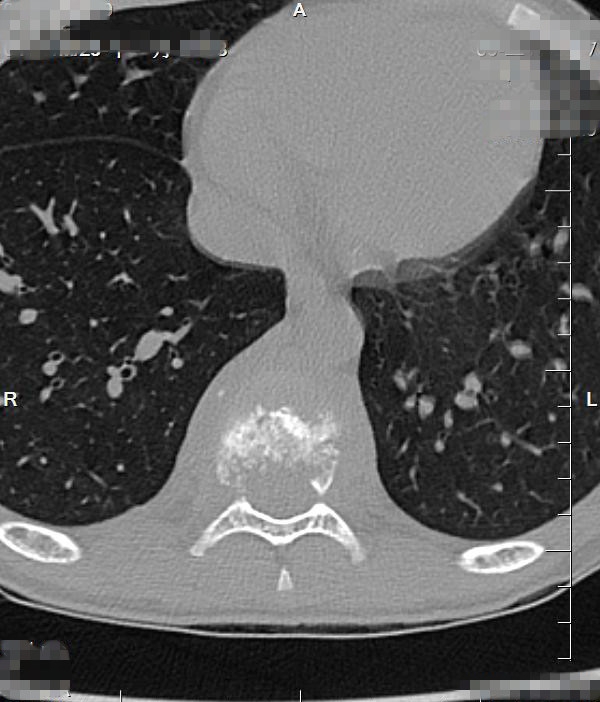

入院CT:结合MRI考虑,T9椎体病理性压缩性骨折,双侧椎弓根骨折,伴周围软组织感染性改变。

CT